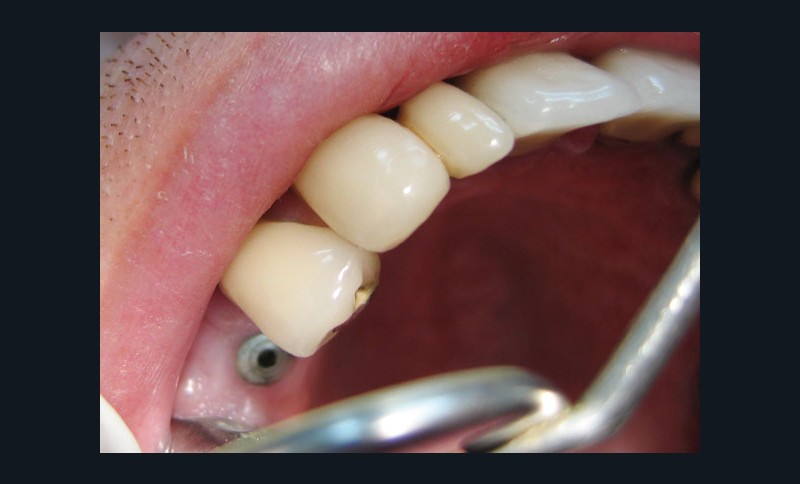

Dépose de la vis de cicatrisation (fig. 4) : l’assistante présente au praticien l’embout du tournevis adapté à la tête de vis de cicatrisation (fig. 5).